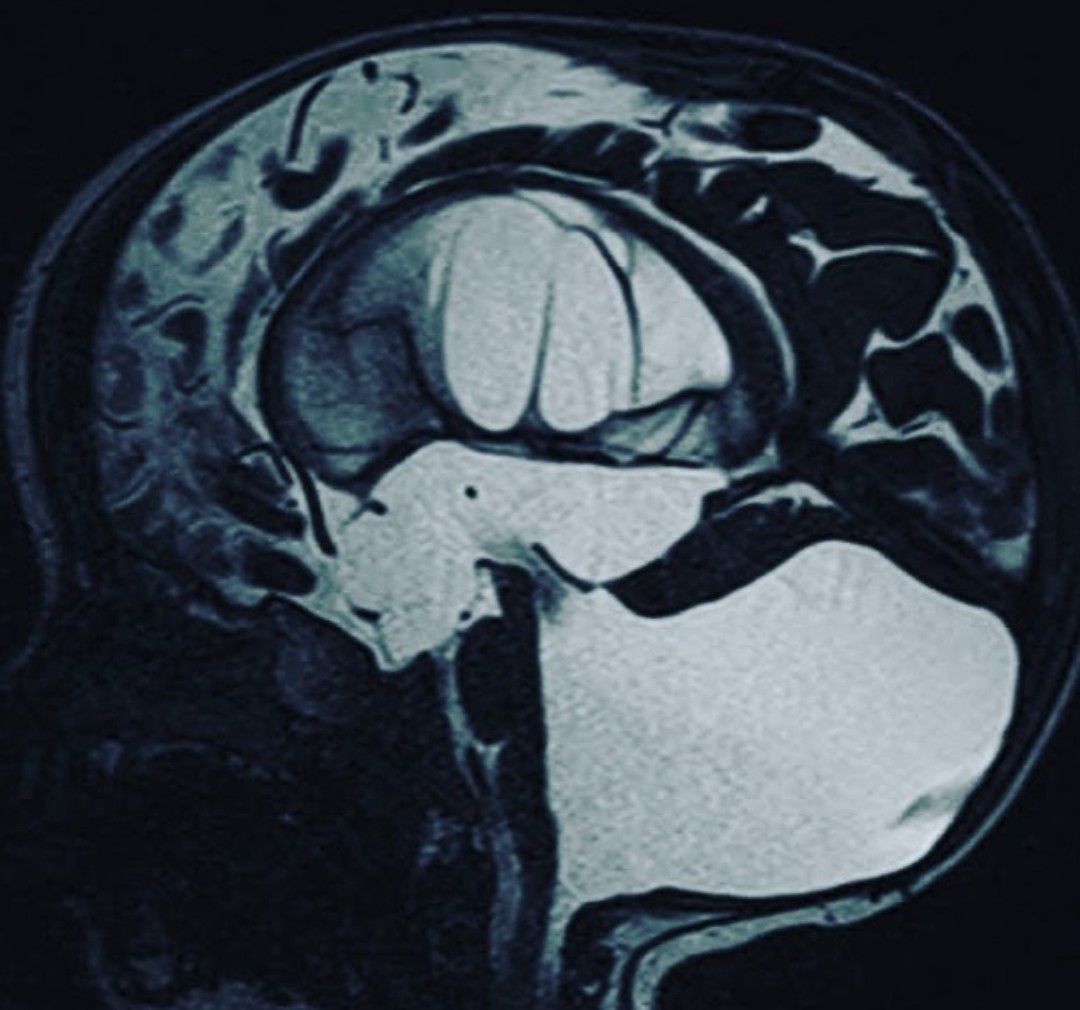

Dandy-Walker Syndrome (DWS) is a congenital (happening before birth) condition where the cerebellum does not develop normally. The cerebellum is an area at the back of the brain that controls movement and balance. With DWS, parts of the cerebellum may never develop or may be very small.